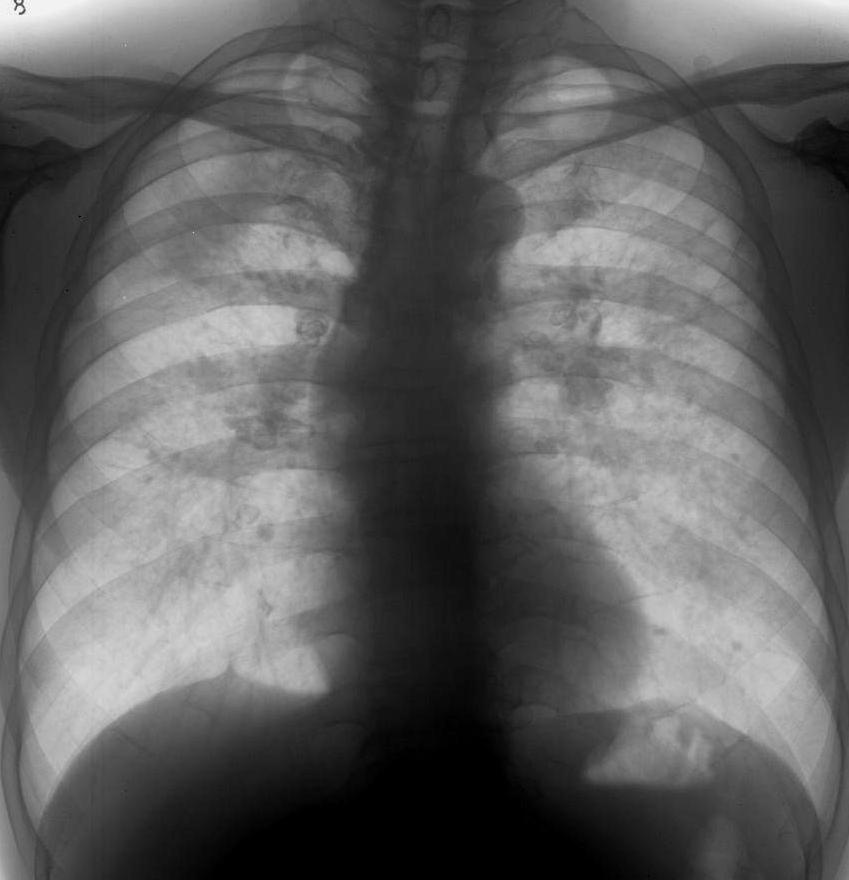

标题: X4980:男,55岁,咳嗽半年余,30余年打石史,20年前发现钙化 [打印本页]

男,55岁,咳嗽半年余,30余年打石史,20年前发现钙化

符合iii期矽肺。

结合病史,考虑矽肺iii期

四、三期矽肺(代号ⅲ)

(一)ⅲ 有大阴影出现,其长径不小于2cm,宽径不小于1cm。

(二)ⅲ+单个大阴影面积或多个大阴影面积的总和超过右上肺区面积者。

矽结节和矽结节融合符合三期矽肺。